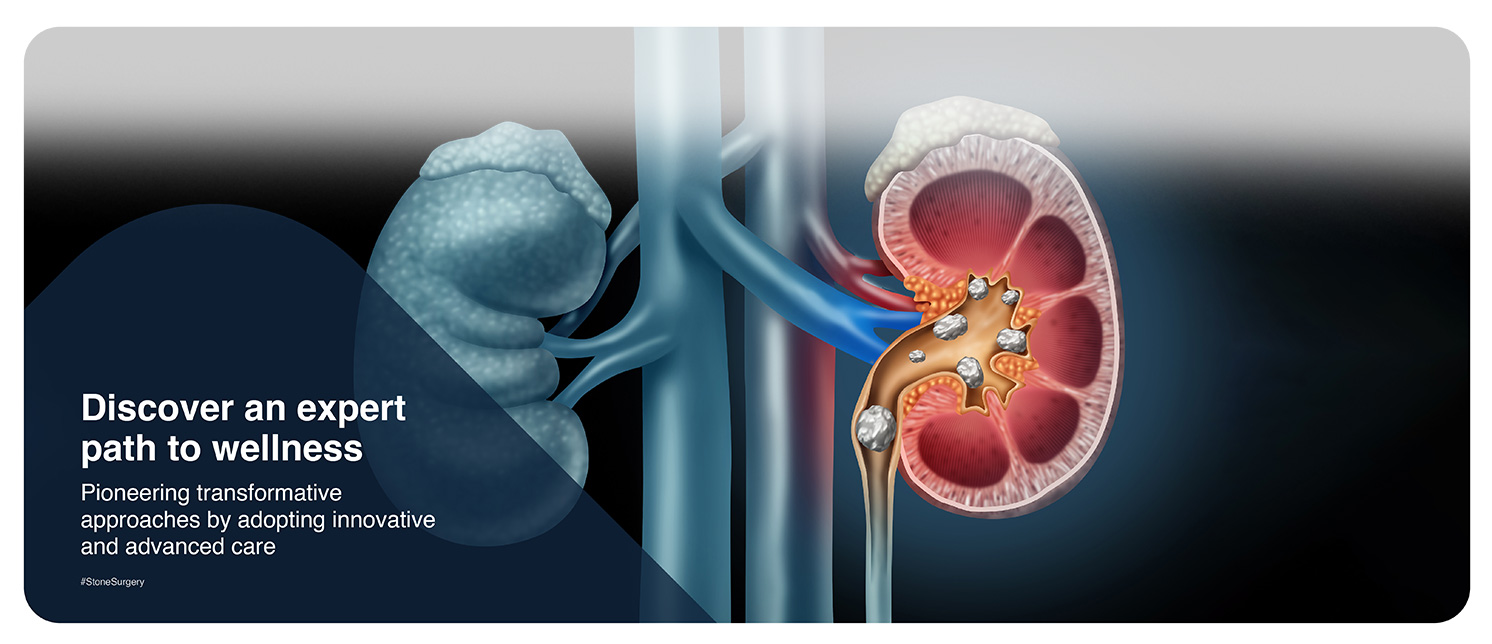

Kidney stones or renal calculi are a result of mineral or salt deposits that form within the kidneys. The size of these stones varies widely and can be as large as a golf ball. Smaller stones may go unnoticed due to the lesser severity of symptoms, whereas larger ones can be extremely painful.

Bladder stones are hard masses that develop in the bladder due to the build-up of unwanted minerals. These are not as common as kidney stones and usually develop when the urine is excessively concentrated. These are also referred to as urinary tract stones or bladder calculi.